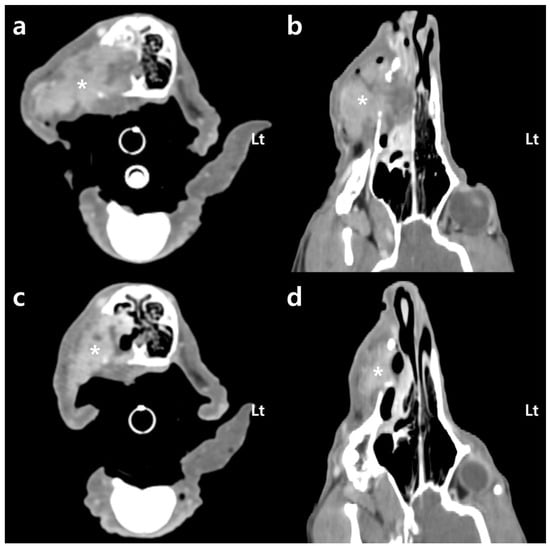

To evaluate the tumor size, the extent of invasion, and metastasis, 64-multi-slice helical CT scans were conducted using a pre- and post-contrast whole-body computed tomography (CT) scanner (Optima CT660, GE Healthcare, Tokyo, Japan). The patient was positioned in ventral recumbency and secured with a custom-made vacuum cushion (Vac-cushion; Chunsung, Seoul, Republic of Korea). Imaging was conducted under specific parameters: 120 kVp, 160 mA, and 1.25 mm slice thickness. A power injector (MEDRAD® Stellant, Bayer, Indianola, PA, USA) was used to administer 600 mg iodine/kg iohexol (Omnipaque™ 300, GE Healthcare, Shanghai, China). Post-contrast computed tomography (CT) revealed a mass with heterogeneous contrast enhancement, measuring up to 41 mm in maximum diameter within the right maxilla. Additionally, evidence of bone erosion was observed in the maxillary bone, turbinate bone, and hard palate adjacent to the oral mass (Figure 2). Furthermore, the mass had invaded the interior of the right nasal cavity. Although metastasis to the regional lymph nodes and distant organs was not definitively identified, the patient was classified as WHO stage 3/4 through CT.

After the first fraction, the hemorrhage was significantly reduced, and, 2 days later, following the second fraction, the hemorrhage stopped. No instances of additional hemorrhage occurred after hemostasis (Figure 4). The hematocrit, initially 19.9% on the day of the first session, gradually increased. After the second session, it reached 25.1% and increased to 39.3% after the third session. Anemia effectively resolved from the third session onward (Figure 5). After the fourth session, both the mean corpuscular volume (69.7 fL; reference range: 60–74 fL) and the mean corpuscular hemoglobin concentration (33.3 g/dL; reference range: 31–36 g/dL) returned to within their respective reference ranges. Additionally, the C-reactive protein level (1.2 mg/L; reference range: 0–10 mg/L) decreased to within the reference range, indicating an improvement regarding inflammation. Following radiation therapy, the previously unmanaged pain diminished. From the fourth session onward, despite no use of analgesics, oral palpation revealed minimal pain response (Colorado State University Veterinary Medical Center Canine Acute Pain Scale 1/4). In addition, food intake improved from the second session onward. Following the final treatment, a contrast-enhanced CT scan was performed to assess tumor size and metastasis changes. A 20.6% reduction in tumor size compared to the pretreatment size was observed by comparing the sum of the maximum diameters of the tumor (Figure 2). However, metastatic changes were strongly suspected in the right mandibular lymph node and lung, based on CT findings, leading to a worsening of the WHO stage to 4/4.

Figure 2. Transverse (a,c) and dorsal (b,d) multiplanar post-contrast computed tomography (CT) images of the patient with a soft tissue algorithm (WL 45; WW 450): (a,b) before radiotherapy, the right maxillary mass (*) reveals heterogeneous enhancement with a maximum diameter of 41 mm. Oral mass shows osteolysis of surrounding bones (maxillary bone, turbinate bone, and hard palate) and invasion into the right nasal cavity; (c,d) immediately after the last radiotherapy session, recognize that the size of the right maxillary mass decreased. When comparing the sum of the maximum diameters, the mass exhibits a 20.6% reduction in size. Lt: left.